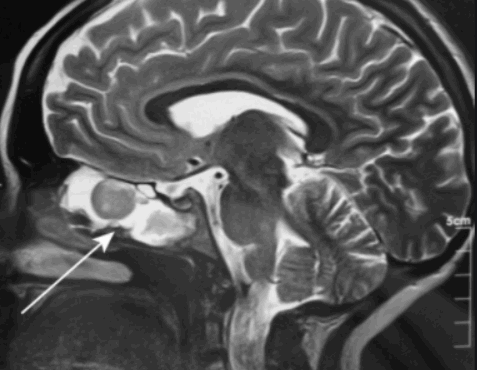

Магнитно-резонансное изображение измененной лобной пазухи